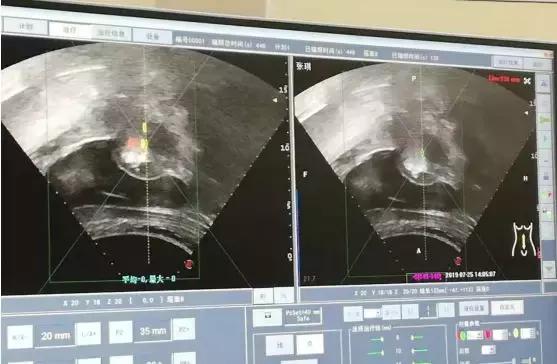

下面四组影像学资料为其中一名子宫肌瘤患者在治疗前、治疗中以及治疗后的影像学表现。

消融术中表现